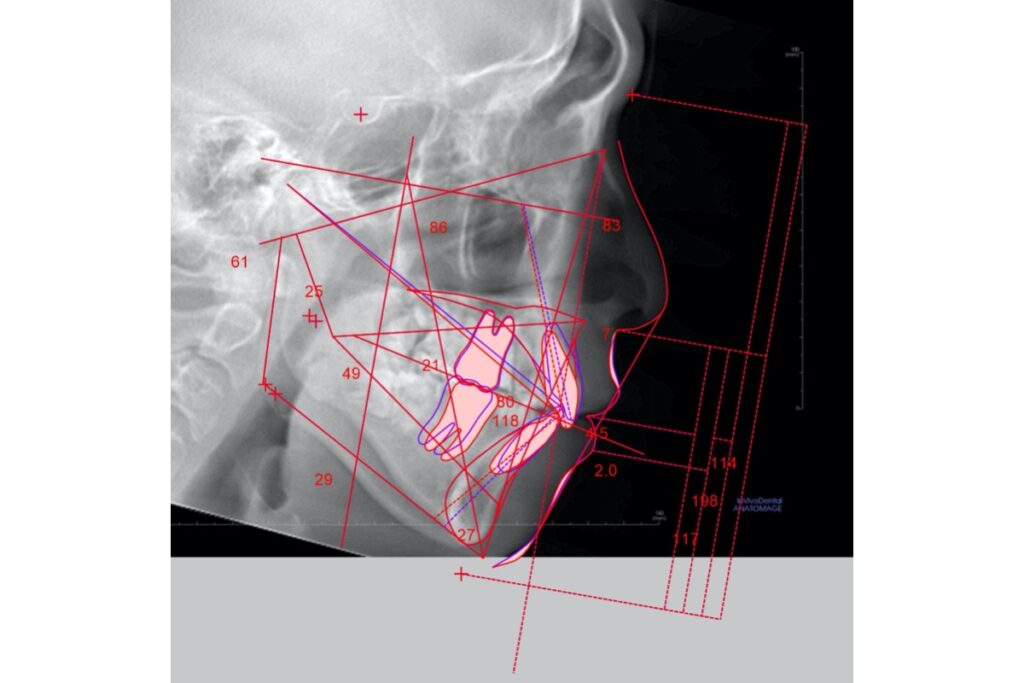

当医院ではレントゲン写真、セファロ撮影、CTやiTeroの3D分析データをもとに矯正専門医により治療計画が立てられます。

診断時には、抜歯の有無や現在の数値から治療後の数値の変化、および顔写真などをもとに患者様が少しでもイメージしやすいよう、説明を行っていますので矯正治療を考えられている患者様は一度、無料カウンセリングにお越しください^^